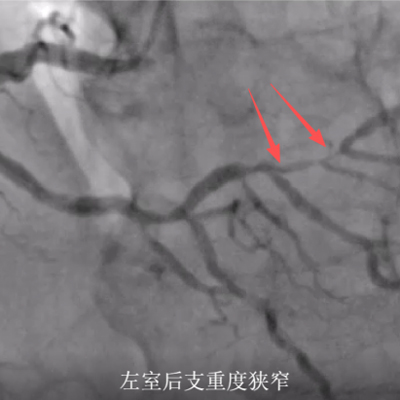

尽管左主干恢复血流,团队在首次手术中发现患者右冠状动脉也存在严重狭窄(约90%)。若同期处理,手术风险高,心脏负荷大。经心脏团队综合评估,决定采取“分期PCI”策略。

一个月后,待李先生心功能有所恢复、整体情况稳定,医疗团队为其施行择期右冠脉介入治疗。此次手术准备充分,过程顺利,于右冠脉狭窄处成功植入支架,彻底解除心脏血管的严重狭窄。

心血管内科朱兴彪主任解释:“针对此类多支血管病变的极危重患者,分期治疗更为科学安全。急诊手术以‘保命’为主,处理罪犯血管;择期手术则在患者稳定状态下处理其他严重病变,旨在‘根治’与‘预防’,最大化降低风险、改善预后。”